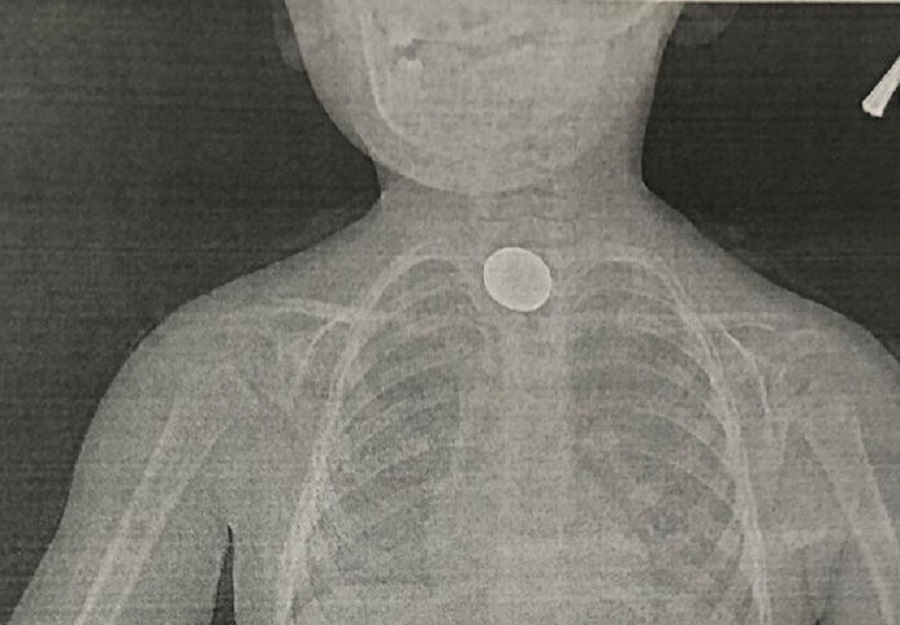

В Городскую больницу №1 Новороссийска поступил 3-летний пациент, проглотивший монету. Его отец рассказал врачам, что мальчику в течение нескольких часов было тяжело дышать, а в груди начались боли. Сам же ребенок во время приема вел себя активно - признаков ухудшения состояния у него не наблюдалось.

- Ребенку в экстренном порядке провели обзорную рентгенографию органов грудной клетки и брюшной полости. По результатам обследования выявлено наличие инородного тела - монета визуализировалась в верхней трети пищевода, - сообщили в пресс-службе больницы.

Уточняется, что под общим наркозом врачи эндоскопического отделения извлекли двухрублевую монету. Мальчик был выписан из стационара на следующий день с условием дальнейшего планового наблюдения педиатром поликлиники по месту жительства.